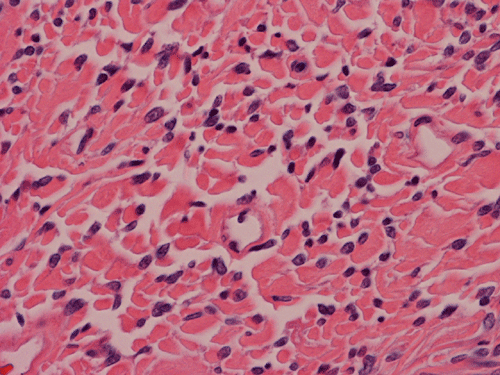

Histologically, the tumor is composed predominantly of strands of collagen fibers arranged in interlacing bundles (Panel F, G, H, I, J ). The histologic pattern is rather homogeneous among different areas and no area with particular hypocellularity or hypercellularity are found (Panel F). In between the collagen fibers are cigar shaped nuclei without high grade features (Panel J). The nuclei and the collagen fibers maintain an interesting regularly randomized relationship reminiscent of a checker board pattern (Panel I). A few small fragments of entrapped, mature bone are also found within the tumor. Mitoses and necrosis are not seen.